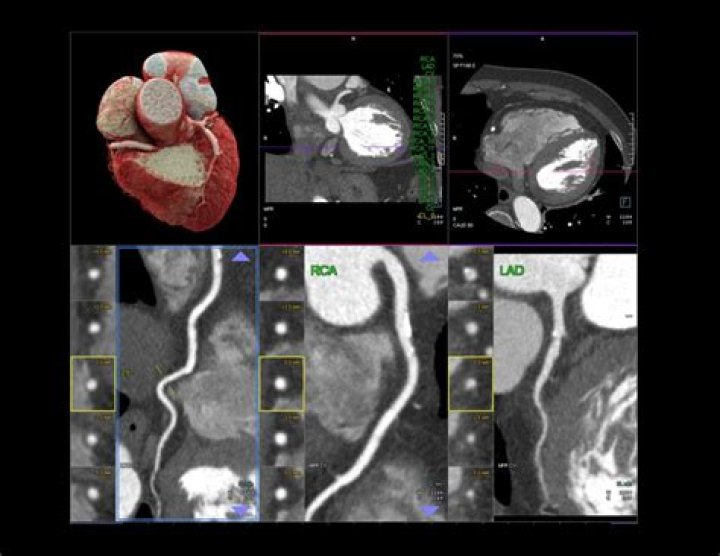

A CT coronary angiogram can reveal plaque buildup and identify blockages in the arteries, which can lead to a heart attack. Prior to the test, a contrast dye is injected into the arm to make the arteries more visible. The test typically takes 30 minutes to complete.

There are several types of CT scans used in the diagnosis of heart disease, including: Calcium-score screening heart scan. Coronary CT angiography (CTA) Total body CT scan.

A heart CT scan shows detailed images of your arteries, aorta, heart and valves, so that healthcare professionals can measure your heart health without an invasive or lengthy procedure. After your heart CT scan in our low-dose Siemens CT scanner, you will receive your coronary calcium score.

What is the difference between a CT scan and a CT angiogram?

Computed tomography (CT) scan is a type of x-ray that uses a computer to take cross-sectional images of your body. Computed tomography angiography (CTA) combines a CT scan with a special dye or contrast material to produce pictures of blood vessels and tissues in a section of your body.